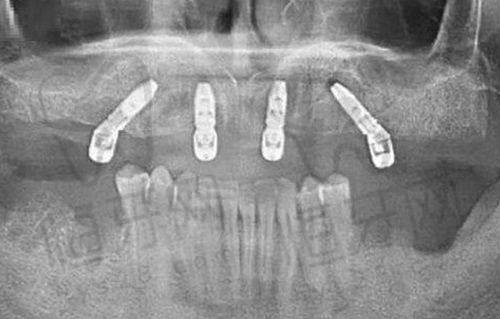

扬州贝恩口腔医院作为当地知名的口腔医疗机构,其收费标准在业内也颇具竞争力。医院的收费体系透明,患者在接受治疗前可以清晰了解各项费用。比如,种植牙的价格根据不同的品牌和技术有所差异,美国皓圣种植牙价格为4855.74元起,而德国ICX种植牙则为6502.6元起。此外,医院还提供儿童肌功能矫正、牙齿美白等项目,价格相对合理,窝沟封闭仅需150元,全口涂氟也只需20元,极大地满足了不同患者的需求。

扬州金铂利口腔医院在收费标准上同样具备竞争力,尤其是在种植牙和牙齿矫正方面。医院的种植牙价格从2920元起,到高端的瑞典诺贝尔种植牙则高达21000元。而在牙齿矫正方面,时代天使隐形矫正的价格为19800元起,陶瓷非自锁托槽矫正则为18000元起,价格范围广泛,能够满足不同患者的需求。